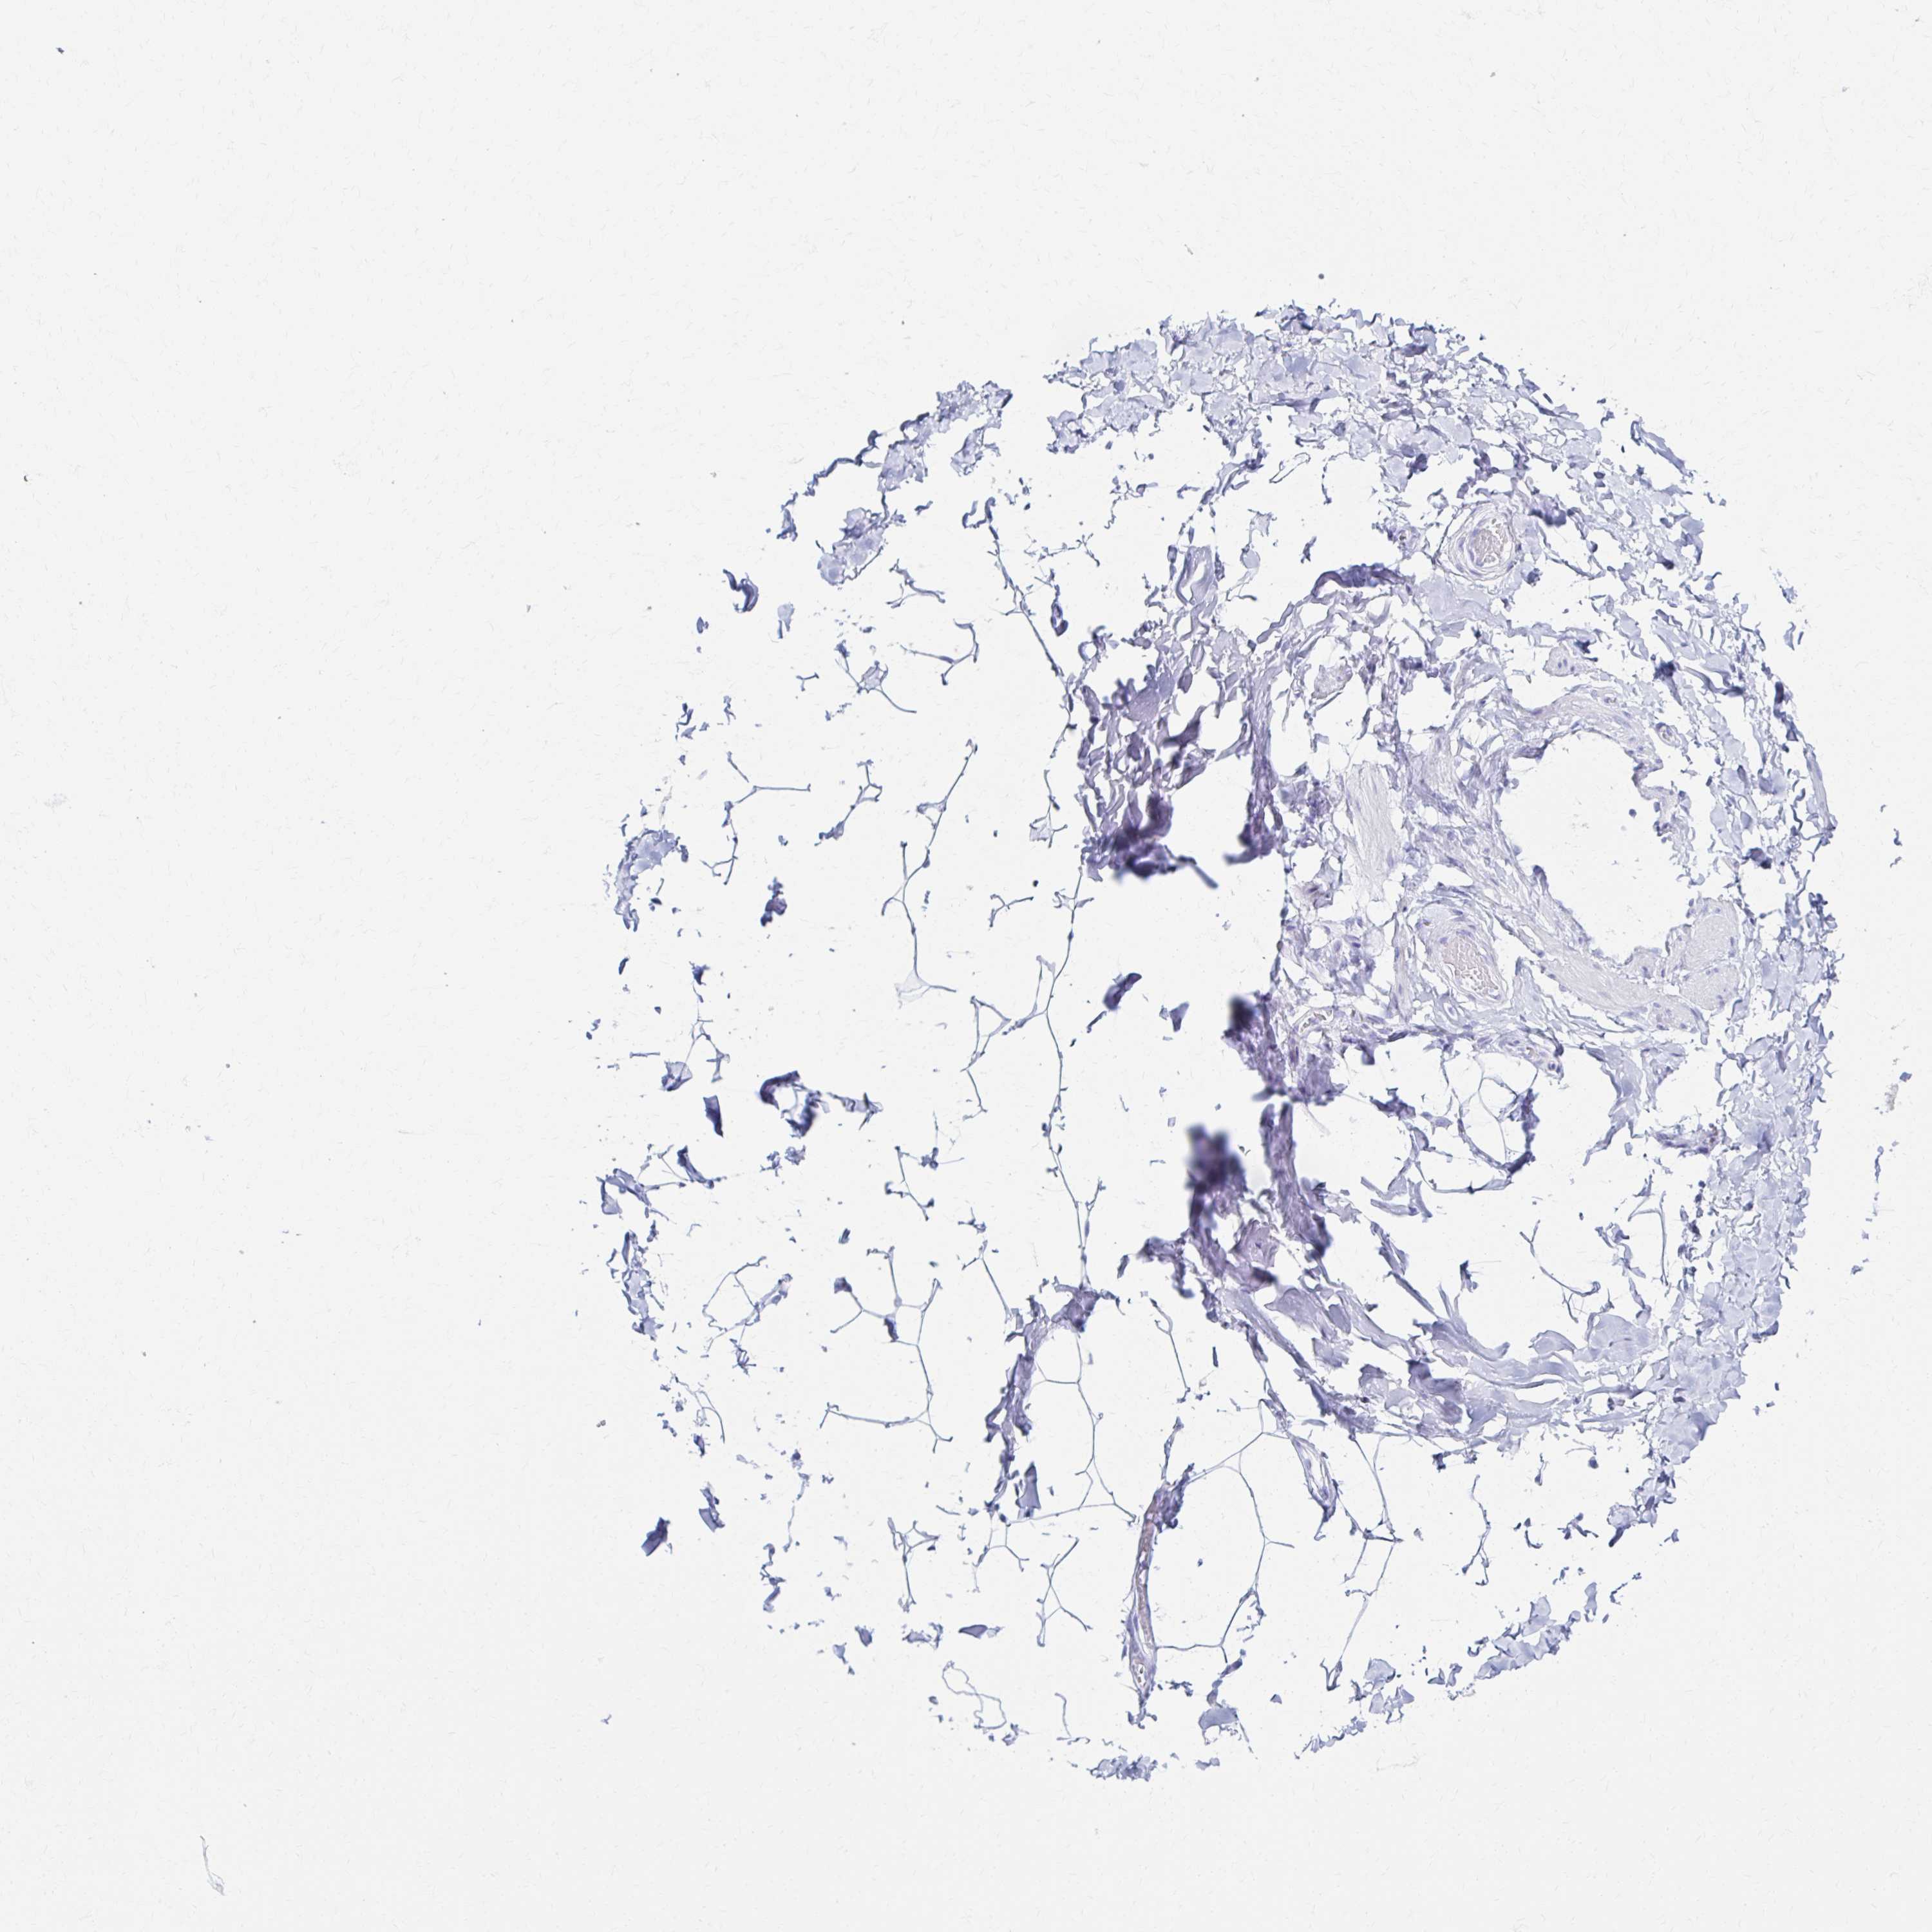

PRKCG